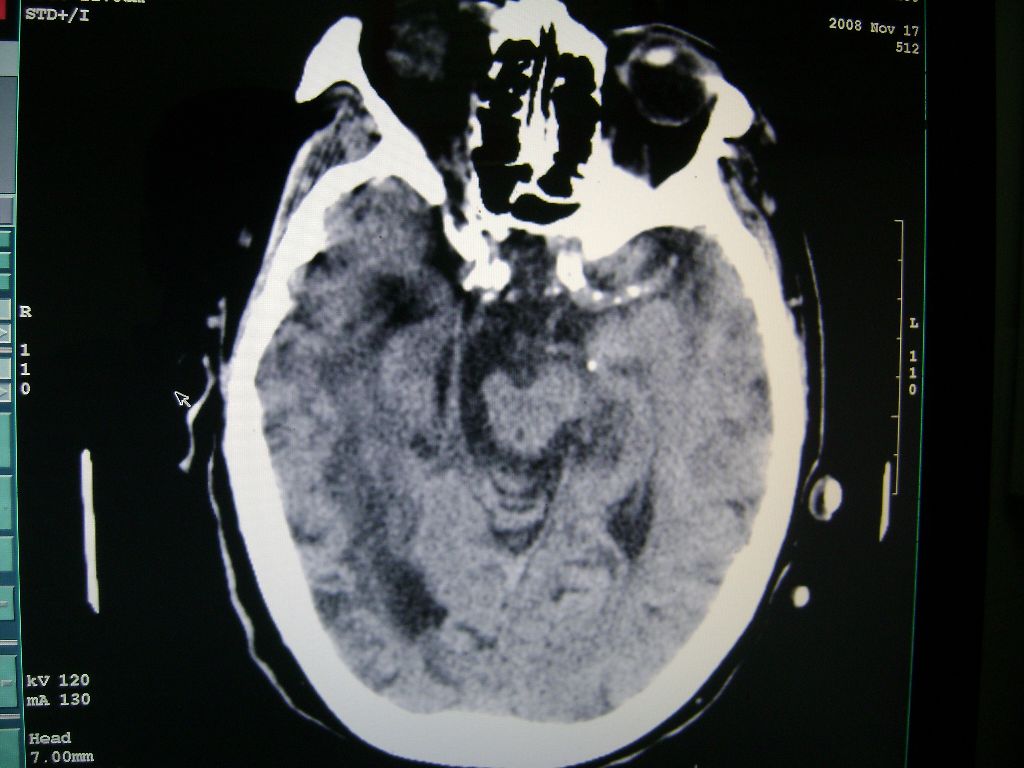

右侧额颞枕顶叶脑软化灶,脑萎缩,大脑中动脉壁钙化。

右侧半球陈旧性卒中,不除外伴有新病灶,左额叶梗塞,双侧大脑中动脉钙斑

1)右侧额颞枕顶叶脑软化灶;其内高密度影,多为钙化灶。2)脑萎缩。3)大脑中动脉钙化。

右侧陈旧脑梗塞伴脑萎缩。脑内点状钙化。大脑中动脉壁钙化灶。无出血灶。

1)右侧额颞枕顶叶脑软化灶并钙化灶可能。2)脑萎缩。3)大脑中动脉钙化。 -